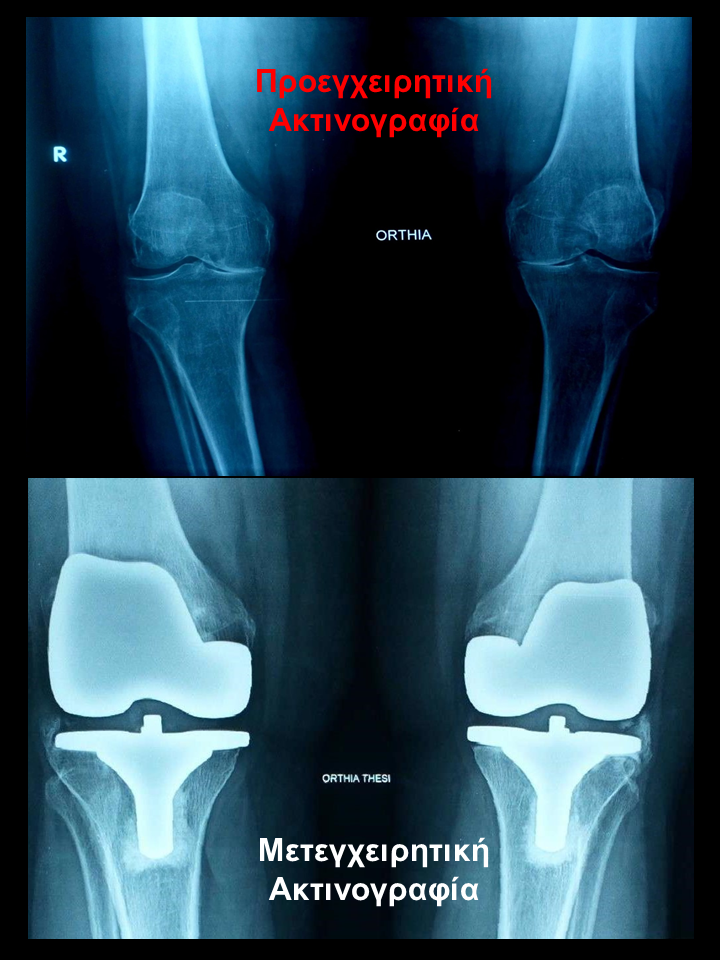

Ρομποτική αρθροπλαστική και στα 2 γόνατα στο ίδιο χειρουργείο

Ασθενής 75 χρονών με οστεοαρθρίτιδα και στα 2 γόνατα. Είχε επιδεινούμενο άλγος τα τελευταία 2 χρόνια που την δυσκόλευε στη βάδιση και την αφυπνούσε το βράδυ. Υπεβλήθη σε ρομποτική αρθροπλαστική και στα 2 γόνατα την ίδια ημέρα. Χρησιμοποιήθηκε η τεχνική διατήρησης οστού όπου αφαιρέθηκαν λιγότερα χιλιοστά οστού. Ο άξονας στο αριστερό γόνατο από 100 αποκαταστάθηκε στις 00 και ομοίως στο δεξί. Η κάμψη στο αριστερό αποκαταστάθηκε στις 1160 . Η ασθενής βαδίζει πλέον χωρίς καμία ενόχληση.